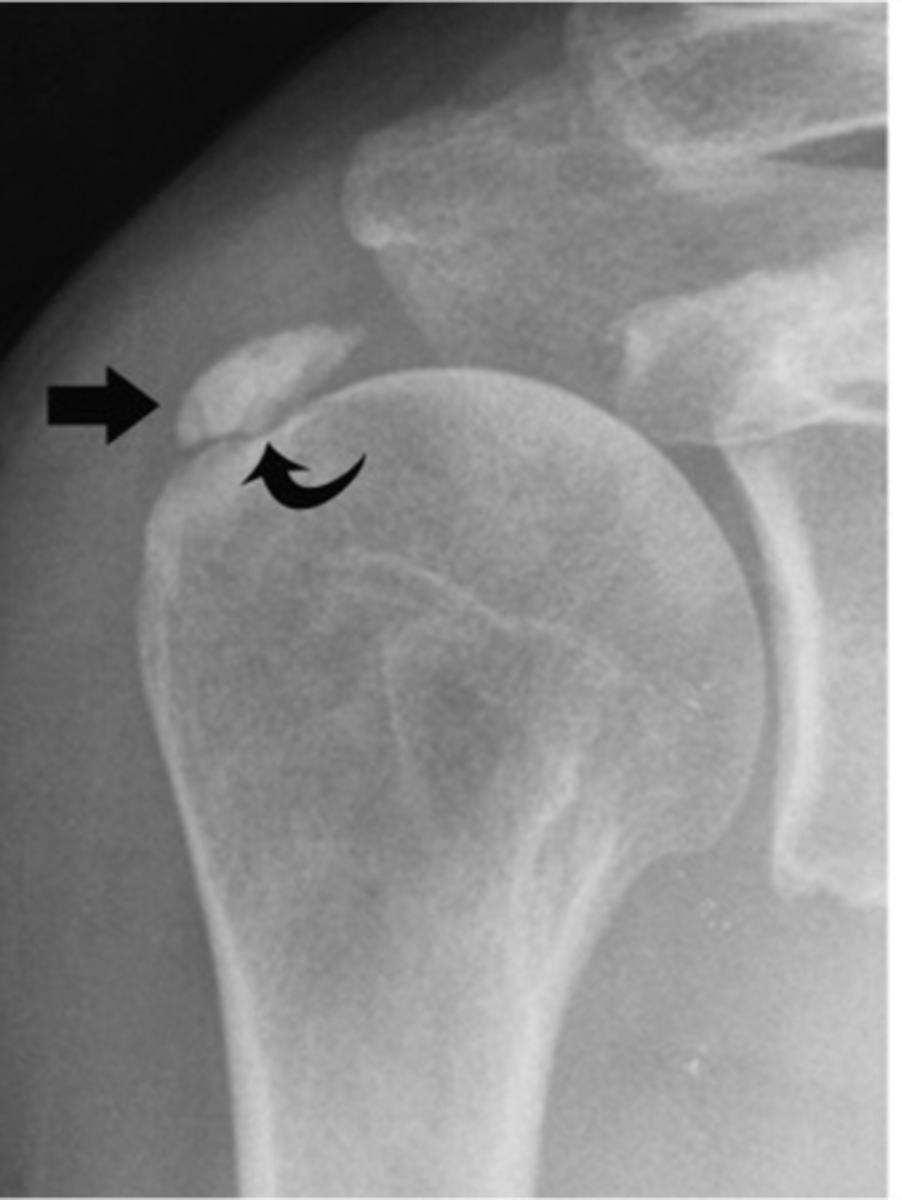

- Deposition of calcium hydroxyapatite within a tendon, bursa, or other periarticular soft tissue

- May cause tendinitis, bursitis, and joint pain

- 40-70 y.o.a

- M=F

- Pain, tenderness, localized swelling

- Decreased ROM

State the clinical features of hydroxyapatite deposition disease (HADD)

Calcific tendinitis

Another term for hydroxyapatite deposition disease (HADD)

Supraspinatus

Hydroxyapatite deposition disease (HADD) of the _____